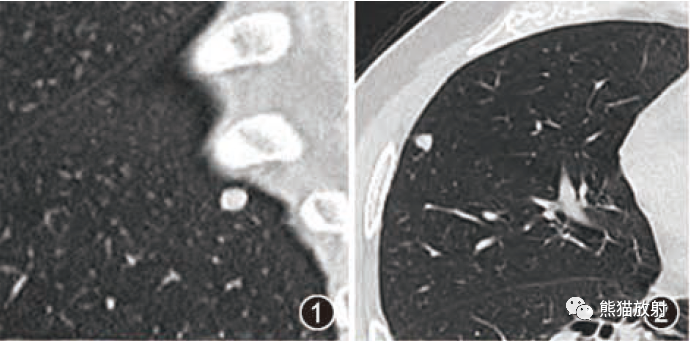

张力性纵隔气肿影像表现及严重度分级  迅速增大的肺部结节,首先考虑良性,确诊需要肺穿

迅速增大的肺部结节,首先考虑良性,确诊需要肺穿  肺隔离症:易误诊为肺癌的占位性病变,肺穿刺禁忌!

肺转移瘤的十种不典型CT表现  肺内淋巴结的CT表现特点及与病理对照